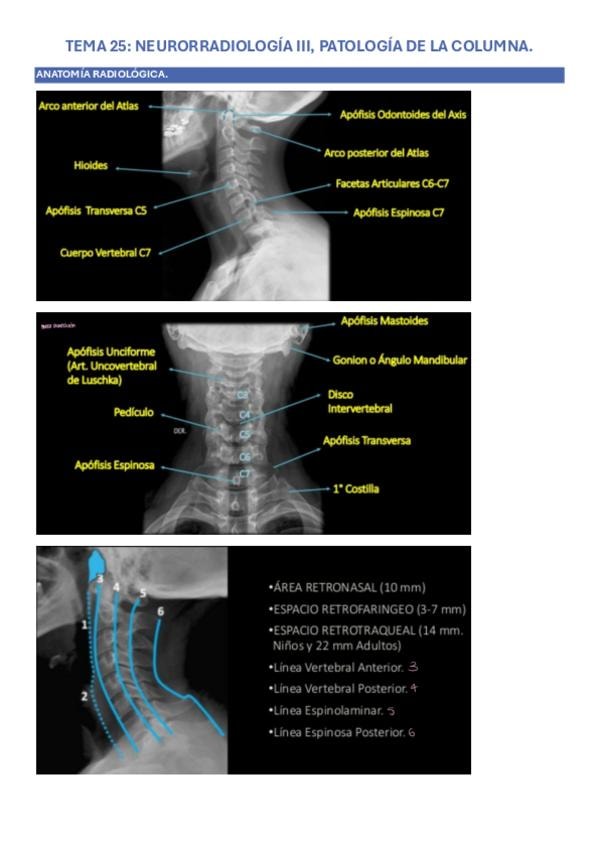

TEMA-25-Rx.pdf

Apuntes - TEMA-25-Rx.pdf